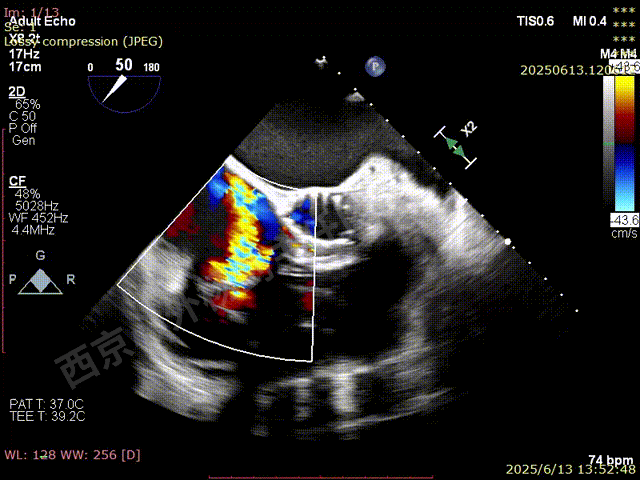

二尖瓣后叶栓系严重,前叶相对错位,反流束沿2区分布广泛,2偏3区处存在反流。

反流宽度至少23mm,因影像调整困难,考虑实际反流更宽。